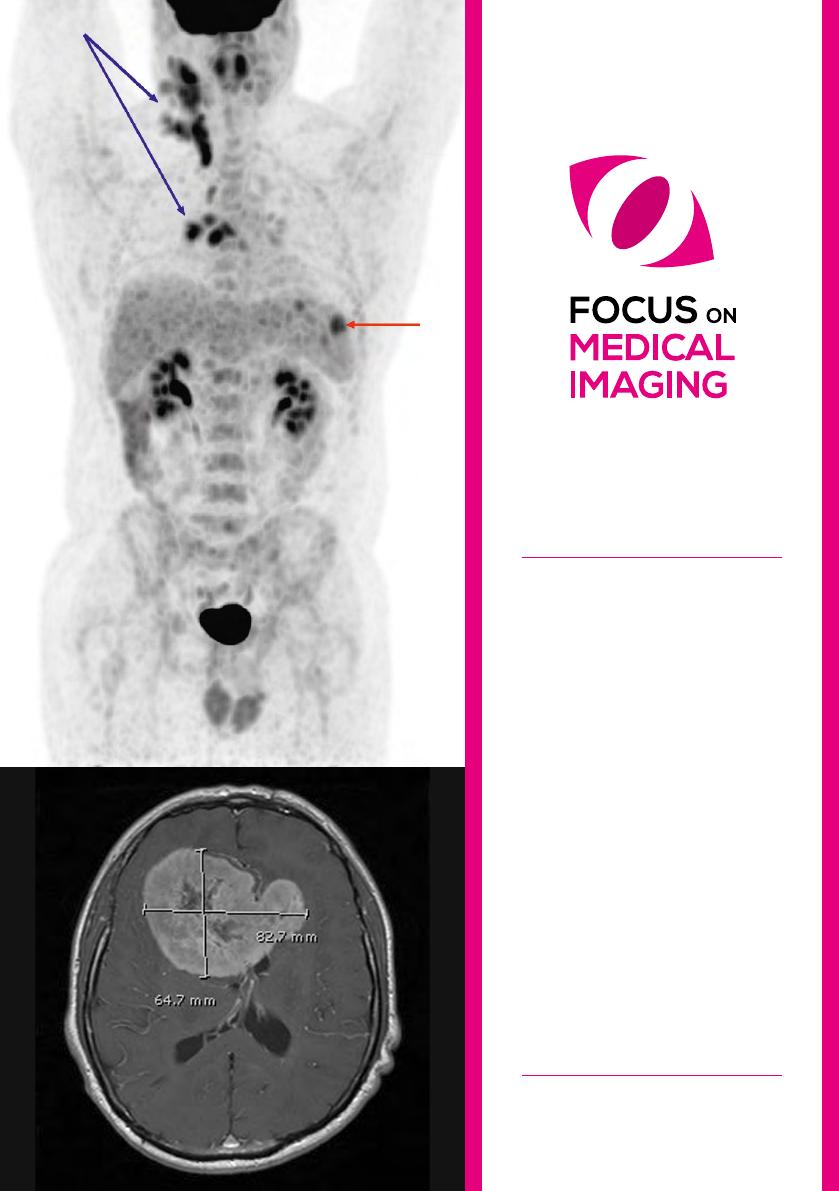

de Hodgkin. Le type d’examen d’imagerie à

réaliser dépend de l’avidité de la maladie pour

le [

18

F]fluorodéoxyglucose (FDG) (Figure 1). La

tomographie à émission de positons couplée à une

tomodensitométrie (PET/CT) est recommandée

pour les lymphomes avides en FDG. Lorsque le

lymphome n’est pas avide en FDG, le CT seul

est recommandé. Après traitement, l’ensemble

des examens anormaux lors du bilan initial est

répété afin d’évaluer la réponse thérapeutique. En

cas de maladie de Hodgkin ou de LNH agressif,

la survie prolongée n’est possible que pour les

patients en rémission complète.